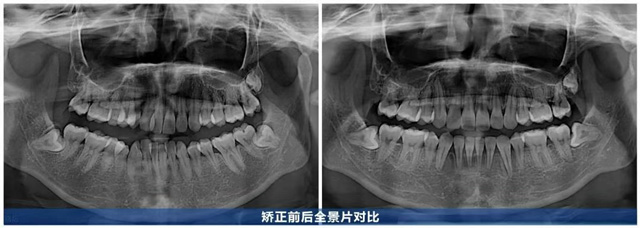

初診時,魯維希主任通過系統檢查發現何女士存在復合型口腔問題:上下頜笑弧和笑線不協調,牙列擁擠現象明顯,特別是上頜重度擁擠、下頜中度擁擠,門牙也明顯傾斜,同時還伴有深覆合的問題,不僅影響面部美觀,使得她的笑容大打折扣,還嚴重影響口腔清潔,易埋下諸多口腔隱患。

針對何女士的情況,魯維希主任經過專業評估后制定了分階段治療計劃:為改善牙齒擁擠及深覆合情況,先拔除四顆牙齒獲取間隙,通過對間隙的分析,在整個治療的過程中,對牙頜系統的矢狀向、水平向、垂直向進行精準控制。

蝶變:微微一笑很傾城

歷時2年,何女士的牙齒煥然一新:曾經擁擠的牙齒排列有序,前牙深覆合改善,咬合關系恢復正常,笑起來牙弓弧度流暢自然,笑容更舒展了。從正面看,牙齒排列與唇形勾勒出協調的“微笑曲線”,上前牙顯露量恰到好處,牙齦幾乎不外露,面部線條更柔和,笑容也更顯柔和自信。